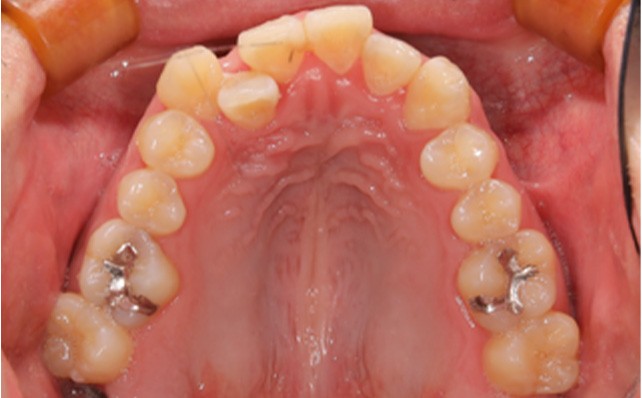

治療前

主訴 ガタガタな歯並びを治したい

虫歯になりやすい

治療内容 ラビアルマルチブラケット装置を用いた矯正治療

抜歯なし